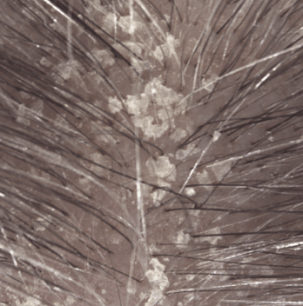

Lo shampoo KERTYOL PSO è specialmente indicato per la cura del cuoio capelluto soggetto a psoriasi.

La sua formula innovativa agisce a tutti i livelli della fisiopatologia della psoriasi. Lo shampoo trattante può essere utilizzato in associazione a trattamenti dermatologici specifici, in alternanza o come mantenimento per limitare la ricomparsa delle placche.

Principio attivo cheratolitico che induce una significativa perdita di coesione dello strato corneo: desquamazione delle placche ispessite del cuoio capelluto.

Risultati di efficacia

Spessore delle placche dopo 1 mese (3)